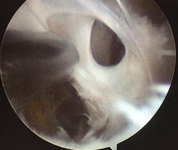

Septae within a popliteal cyst

From the collection of Dr John D. Kelly IV; used with permission

Synovitis within cyst